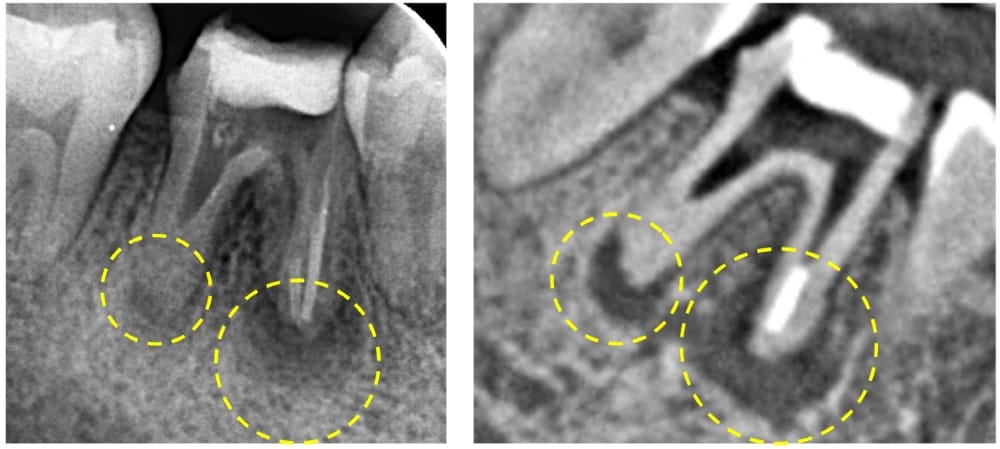

レントゲン・CT画像にて、右下第一大臼歯の根尖部に、明瞭な骨吸収像が認められます。来院時には根管治療の途中の状態でしたが、内部に虫歯が残っており、感染源が取り除けていない状態でした。急性炎症に対して確実な即効性がある治療はありませんが、最大限感染を除去し、細菌の侵入を防ぐことを第一に応急対応を行いました。

術後6ヶ月が経過時点でのレントゲン・CT画像では、もともとはっきりと写っていた根の先の黒い部分は消失し、骨の回復が認められます。痛みも全くなくなり、治癒していると判断し、最終補綴(かぶせもの)を行うことになりました。